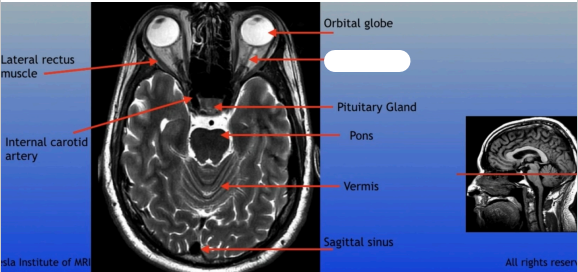

Lateral Rectus Muscle

Internal Carotid Artery

Orbital Globe

Pituitary Gland

Pons

Vermis

Sagittal Sinus